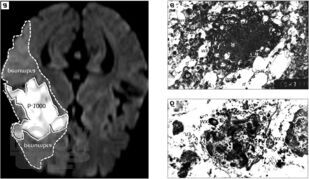

Диагностика острого нарушения мозгового кровообращения совершенствуется в соответствии с прогрессивным развитием лучевых технологий диагностики, что требует определенного обновления информационных материалов с большей детализацией трактовки получаемых данных. Качественно и оперативно полученные сведения становятся основой для клинического решения при выборе методов специализированной помощи. Современный Порядок оказания помощи больным с ОНМК требует раннего определения причинно-следственных связей развития острой цереброваскулярной катастрофы и проведения динамической оценки патогенетических процессов повреждения вещества головного мозга, что возможно только при условии тесного взаимодействия нейрорадиологов и неврологов.

В монографии изложены наиболее полно изученные, наименее спорные и широко применяемые в современной рутинной практике клинико-инструментальные диагностические закономерности, отражающие патогенетическую последовательность и гетерогенный характер острого цереброваскулярного повреждения головного мозга. Предложены типовые диагностические алгоритмы, применяемые в остром периоде заболевания.